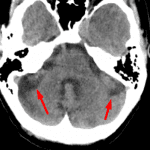

Age: 37

Sex: Female

Indication: Headache